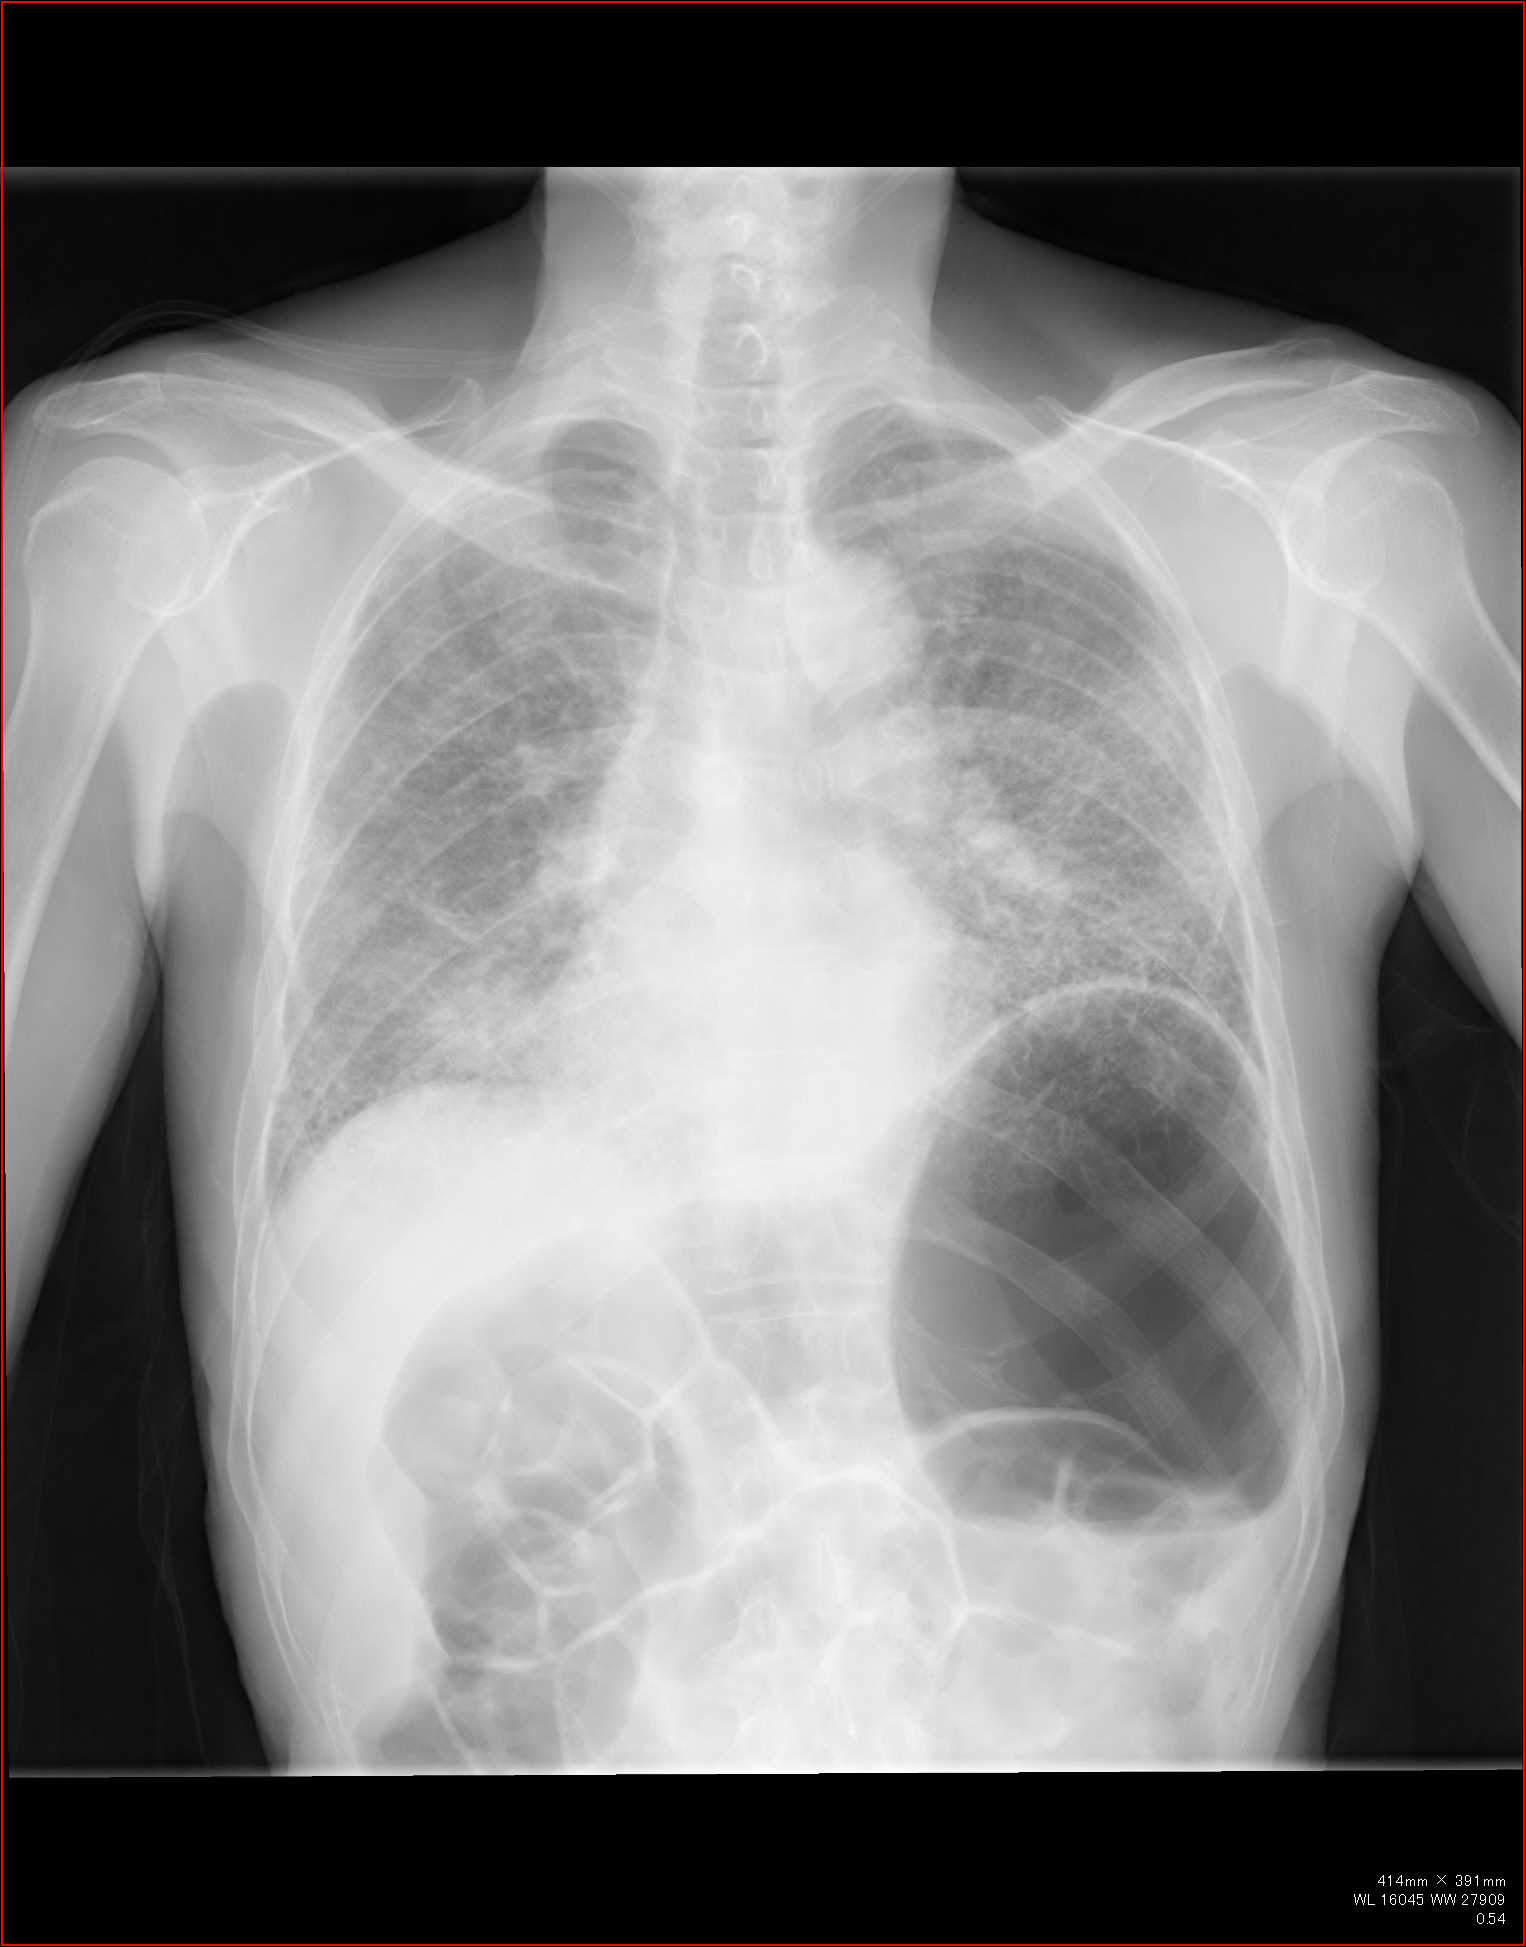

CT全盛の昨今、胸部レントゲン写真の意義は少なく見積もられがちではありますが…。

例えば診療所であったりして、CTはすぐに撮れない、という環境もあるわけです。

また、CTにも弱点があります。

例えば肺の大きさ。

volume

lossや反対に過膨張などの所見は、圧倒的に胸部正面写真がわかりやすいですね。

というわけで、

胸部レントゲン写真で、ここまでわかるか!というところを何回かに分けて、見て参りましょう。

胸部レントゲンの見方、系統的な見方はポリクリやアドバンスでかなり繰り返していますので改めては書きませんが、大事なポイントをおさらいしておきましょう。